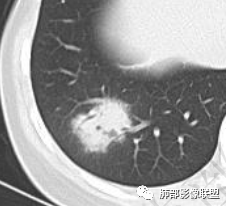

年轻女性,发热,白细胞略低,超敏CRP高,右肺下叶团片影,边缘毛糙,周围见磨玻璃晕,其内含气细支气管,考虑炎性肉芽肿,侵袭性曲霉菌感染?鉴别淋巴瘤

年轻,急性起病,发热伴肺部阴影,考虑感染性病变没问题,无诱因,还是真无诱因,咳嗽无痰,有一些胃肠道症状及乏力。肺部一斑片影,考虑非典型病原菌,治疗无效考虑下特殊病原。这个病程3天,渗出不明显,周围磨玻璃感觉蛮清晰,支气管充气征?鉴别淋巴瘤?

右肺下叶局限性实变影伴晕征。

女,34,畏寒、发热3天,伴纳差、恶心、呕吐。血像不高,ESR、CRP增高。胸部CT:右肺下叶局限斑片影,边缘模糊,内可见支气管穿行,个别层面融冰?肺动脉貌似增粗,考虑不典型病原体感染?肺梗?鉴别淋巴瘤等。

支气管还好吧,鹦鹉热可以表现为球形肺炎,而且这个临床,高热,肺外症状恶心呕吐,白细胞不高,crp高也比较符合。临床是也可以军团,但结合影像还是像鹦鹉热 。

2.影像特征:右肺下叶局限性实变影伴晕征,边界不清,内部支气管尚通畅,实变区密实区边缘稍膨隆。符合炎性病灶特征。

3.综合分析:急性病程,炎性指标高,常见的是普通社区肺炎,如肺炎链球菌感染等。但本例患者临床表现较重,应先表现相对较轻,白细胞不高,须考虑非典型肺炎的可能性。本例隐球菌荚膜实验阴性,而军团菌临床症状一般较重,影像分布也更广泛、进展迅速,多器官损害更明显。因此考虑鹦鹉热衣原体可能性更大一些。其他如腺病毒等感染也是需要排除的。

最终支气管镜灌洗NGS确诊为鹦鹉热衣原体感染。